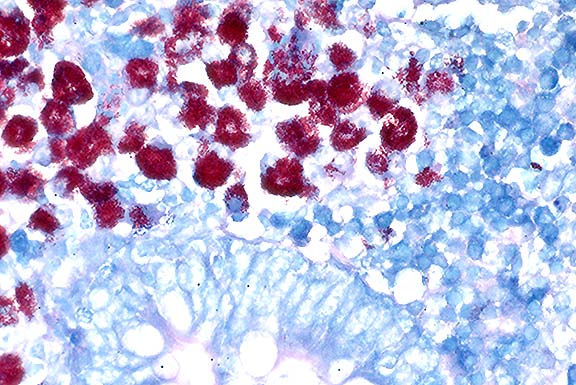

Contributor's Diagnosis and Comments: Enteritis, granulomatous, diffuse, chronic, severe, with diffuse granulomatous lymphadenitis and multifocal lymphogranulomatous phlebitis, lymphangitis and arteritis, mixed breed, adult ovine, caused by acid-fast bacilli, Mycobacterium avium var paratuberculosis, Johne's Disease.

In this case, there is extensive atrophy of normal mucosal

components, which are replaced by an extensive infiltrate of macrophages

into the lamina propria and submucosa, and also with variable

numbers of lymphocytes, plasma cells, neutrophils and eosinophils,

and generally low numbers of Langhans giant cells and epithelioid

macrophages. Peyer's patches are hyperplastic, and mesenteric

attachments are edematous. There are nodular areas of vasculitis

and lymphangitis (not present in all sections). Although the surface

epithelium is absent in most areas, this is interpreted as an

artifact associated with autolysis and not an ulcerative process.

The macrophages throughout the intestinal lesions are distended

with mycobacteria, confirmed by Ziehl Nielsen stains, but apparent

as fine basophilic cytoplasmic stippling in H&E-stained sections.

The lesions are typical for the so-called lepromatous or multibacillary

form of ovine Johne's disease (JD). A second form of the disease

in small ruminants, the paucibacillary form, has few organisms,

few infected macrophages and the inflammatory lesions are predominantly

lymphocytic rather than granulomatous. In this second form, the

diagnosis may be difficult to confirm, either by histopathology

or by culture.